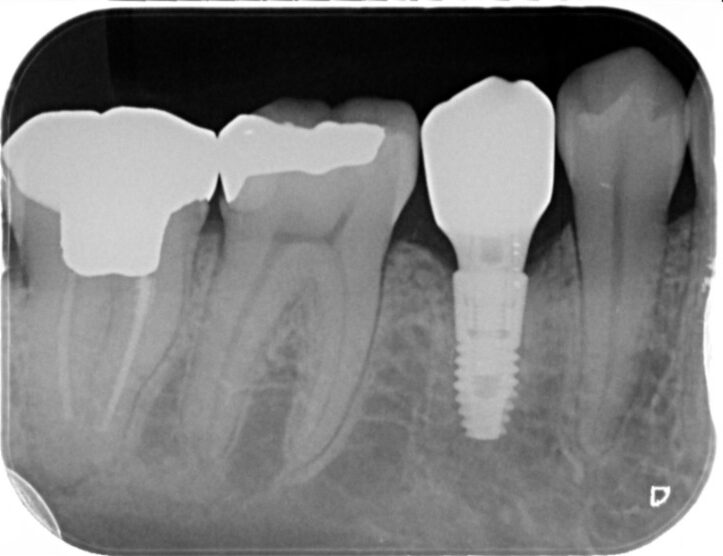

R5.4

左下7のインプラント埋入を検討

左下7番部にエナメル上皮腫(良性腫瘍)が認められた患者様が、将来的にインプラント治療をご希望されました。

まずは安全を最優先に、口腔外科にて腫瘍の摘出手術を行っていただきました。

手術後は、インプラントを支えるための骨がどの程度回復するか慎重に経過を観察し、約2年間、骨の再生を待ちながらフォローアップを続けました。しかし、残念ながら想定したほど骨量が回復せず、理想的な位置(もう少し奥の部位)にインプラントを埋入することが難しい状態でした。

そこで、工学的・解剖学的条件を総合的に検討し、歯科技工士とも綿密に相談した上で、安全性と長期安定性を優先し、手前側の位置にインプラントを埋入するという治療計画に変更しました。

結果としてインプラントは良好に骨と結合し、現在は問題なくお食事もできており、とても満足して生活されているとのことです。

難症例ではありましたが、口腔外科との連携、慎重な経過観察、そして適切な位置へのインプラント埋入により、安全かつ確実な治療結果を得ることができました。